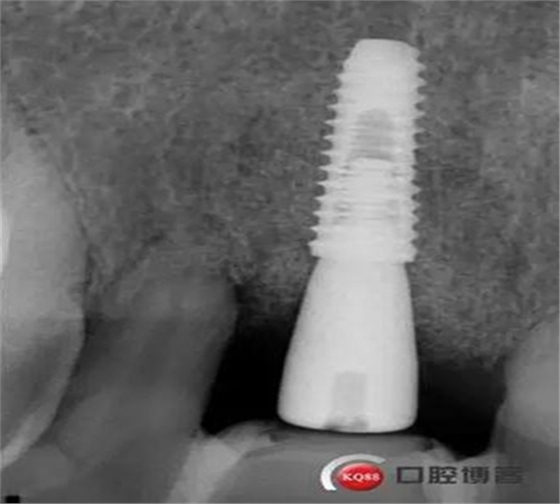

患者:王XX 年齡:42 上前牙松動(dòng)數(shù)年,從未做過任何處理,今來院就診;檢查:CBCT示上前牙區(qū)顎側(cè)一大小約7x7mm囊腫;治療計(jì)劃:即刻種植同期摘除囊腫

術(shù)后CBCT